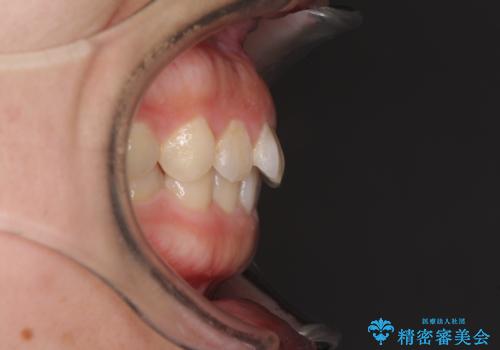

- 前歯のデコボコを治したいとのことで来院された患者様です。

上下顎ともに歯列全体の側方拡大とIPR(歯と歯の間を削る)によってデコボコが解消するように設計し、インビザラインにより治療を行うこととしました。

後方移動に際し、残っていた上顎の親知らずを抜歯することとしました。